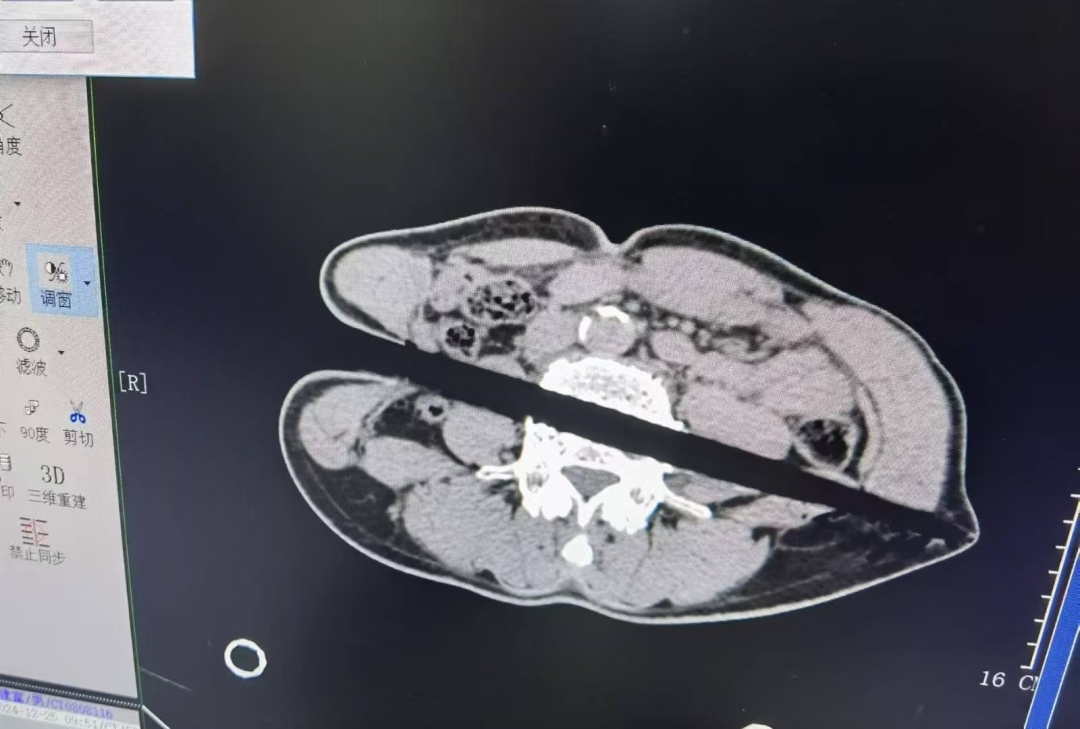

据了解,患者59岁,受伤1小时入院,入院后下肢活动及感觉正常,心率、血压及氧饱和度尚正常,腰部俨然可见一根直径约3厘米的木棍刺入,横穿腹部,另一端到达左侧腰部皮下。患者到达急诊科后,医护人员立即给予监护、吸氧、开放静脉通道、补液处理,普通外科、泌尿外科、骨科等相关科室迅速会诊、完善腹部CT检查及三维重建。CT影像结果显示,木棍经右侧腰部刺入腹部,横穿升结肠、腰大肌及L4椎体达到左侧腹部皮下,降结肠损伤待排。万幸的是木棍避开了重要的血管、神经、肝及肾脾。